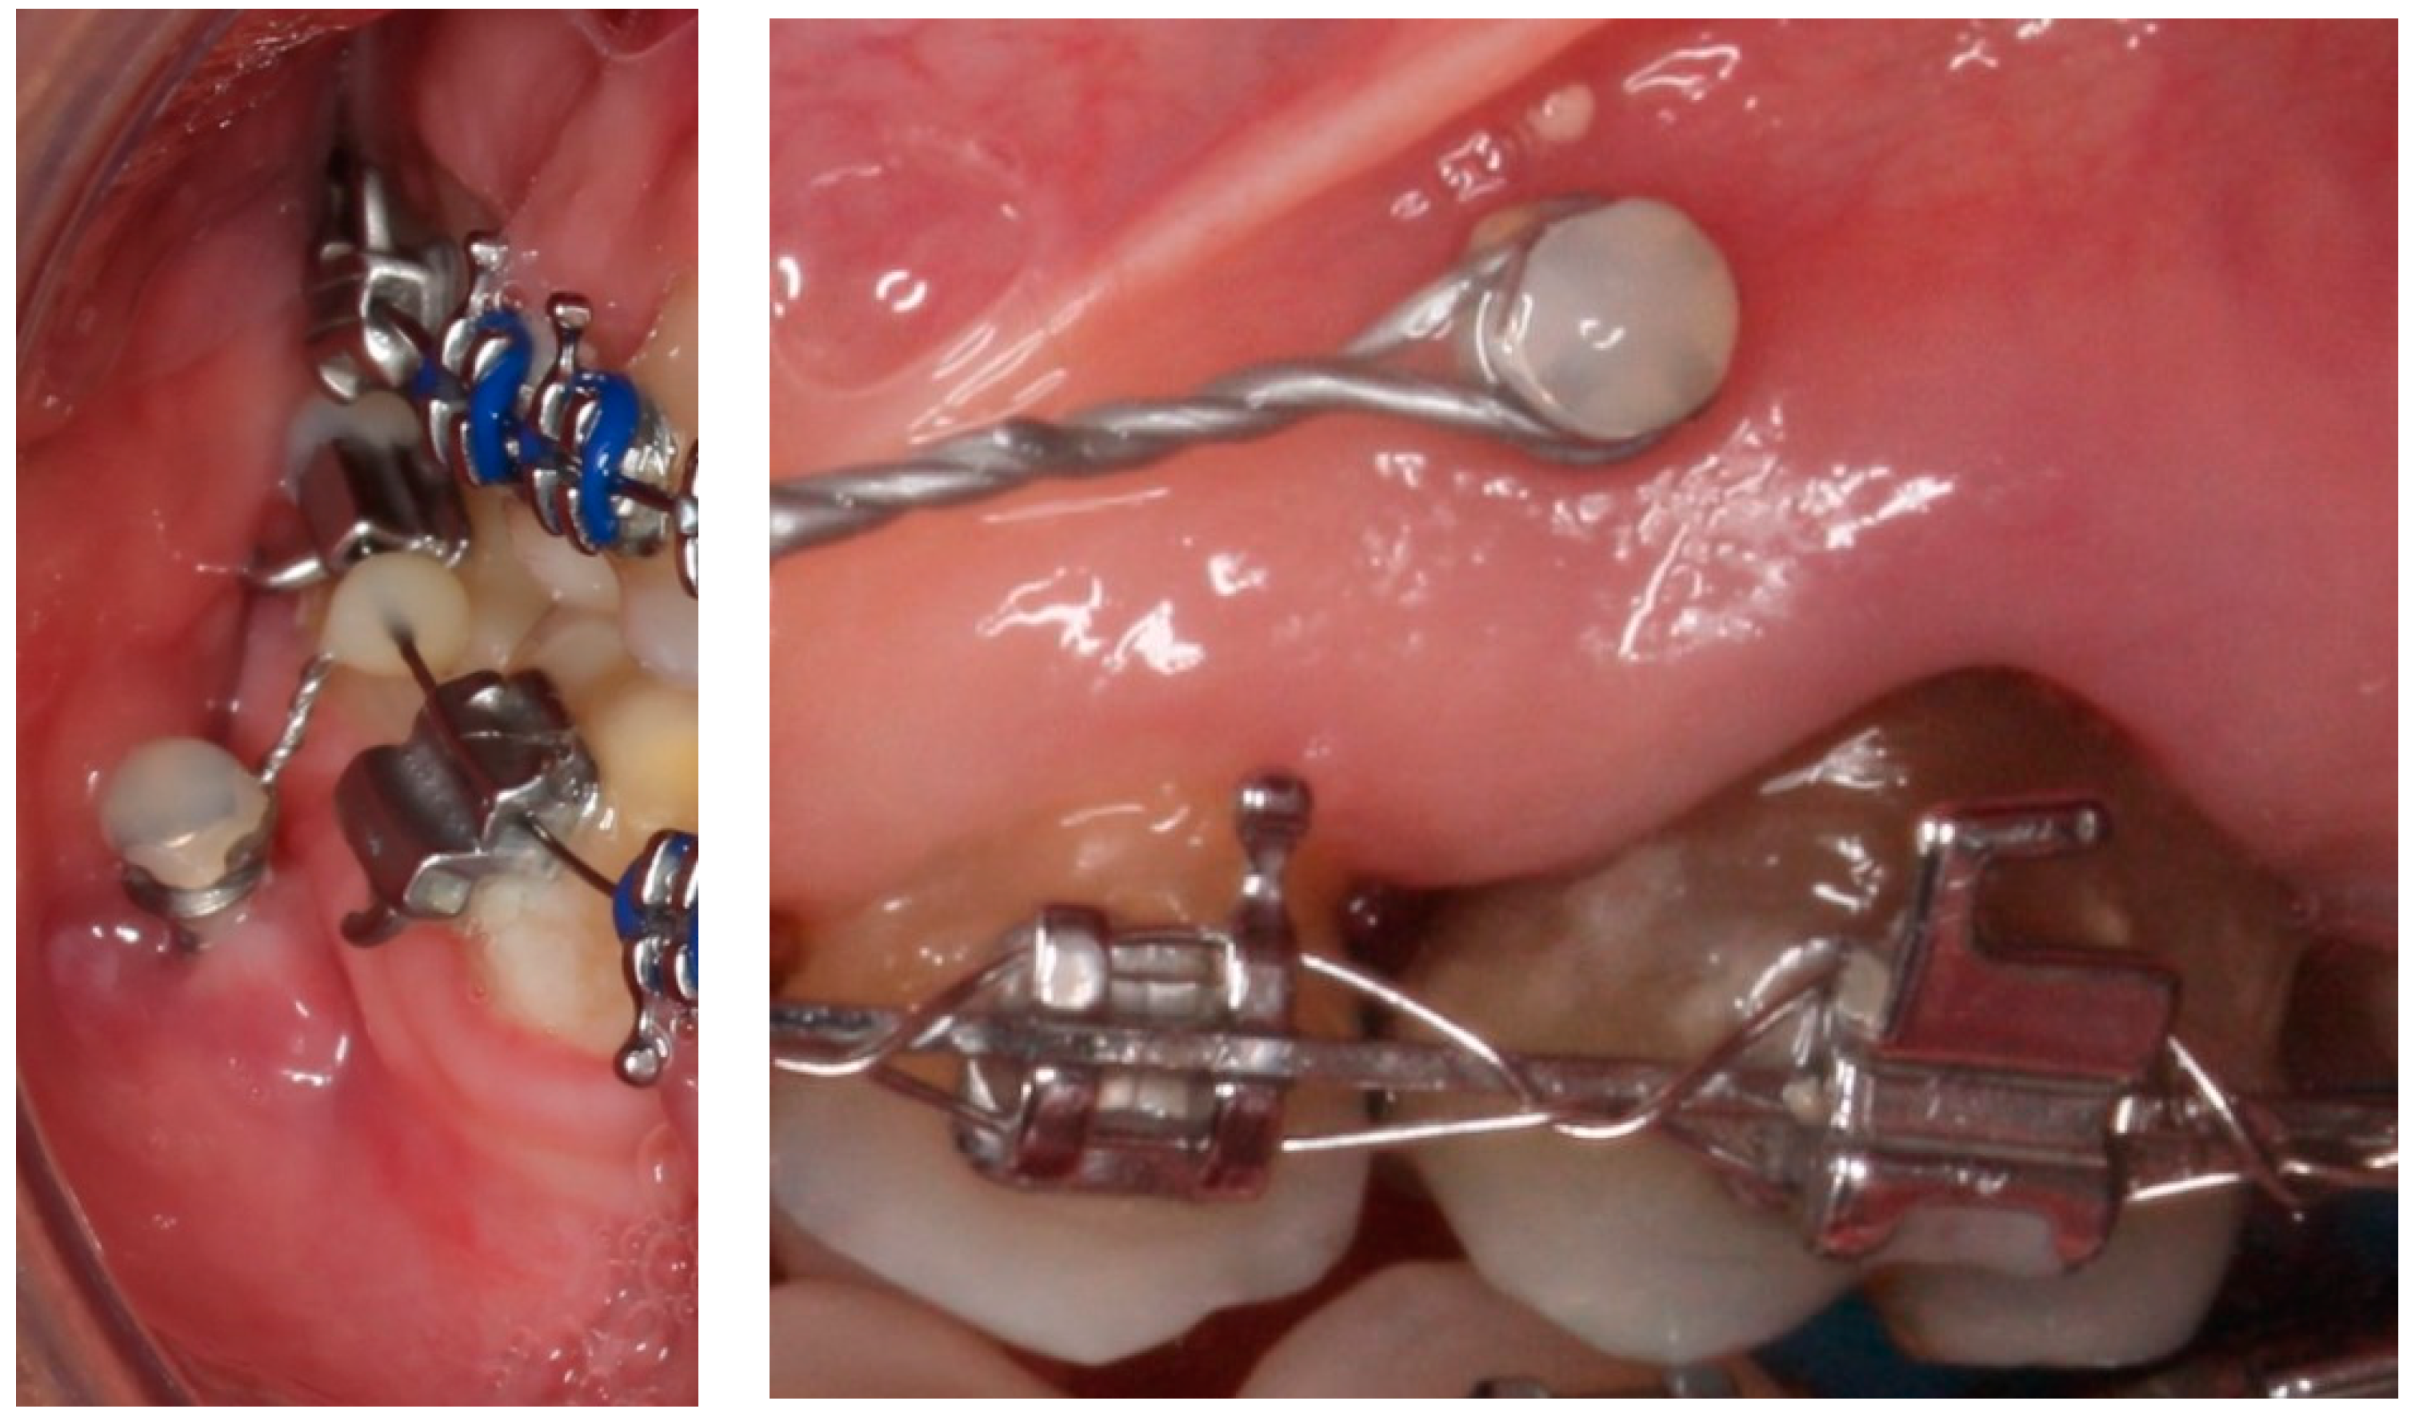

:1. Introduction

2. Materials and Methods